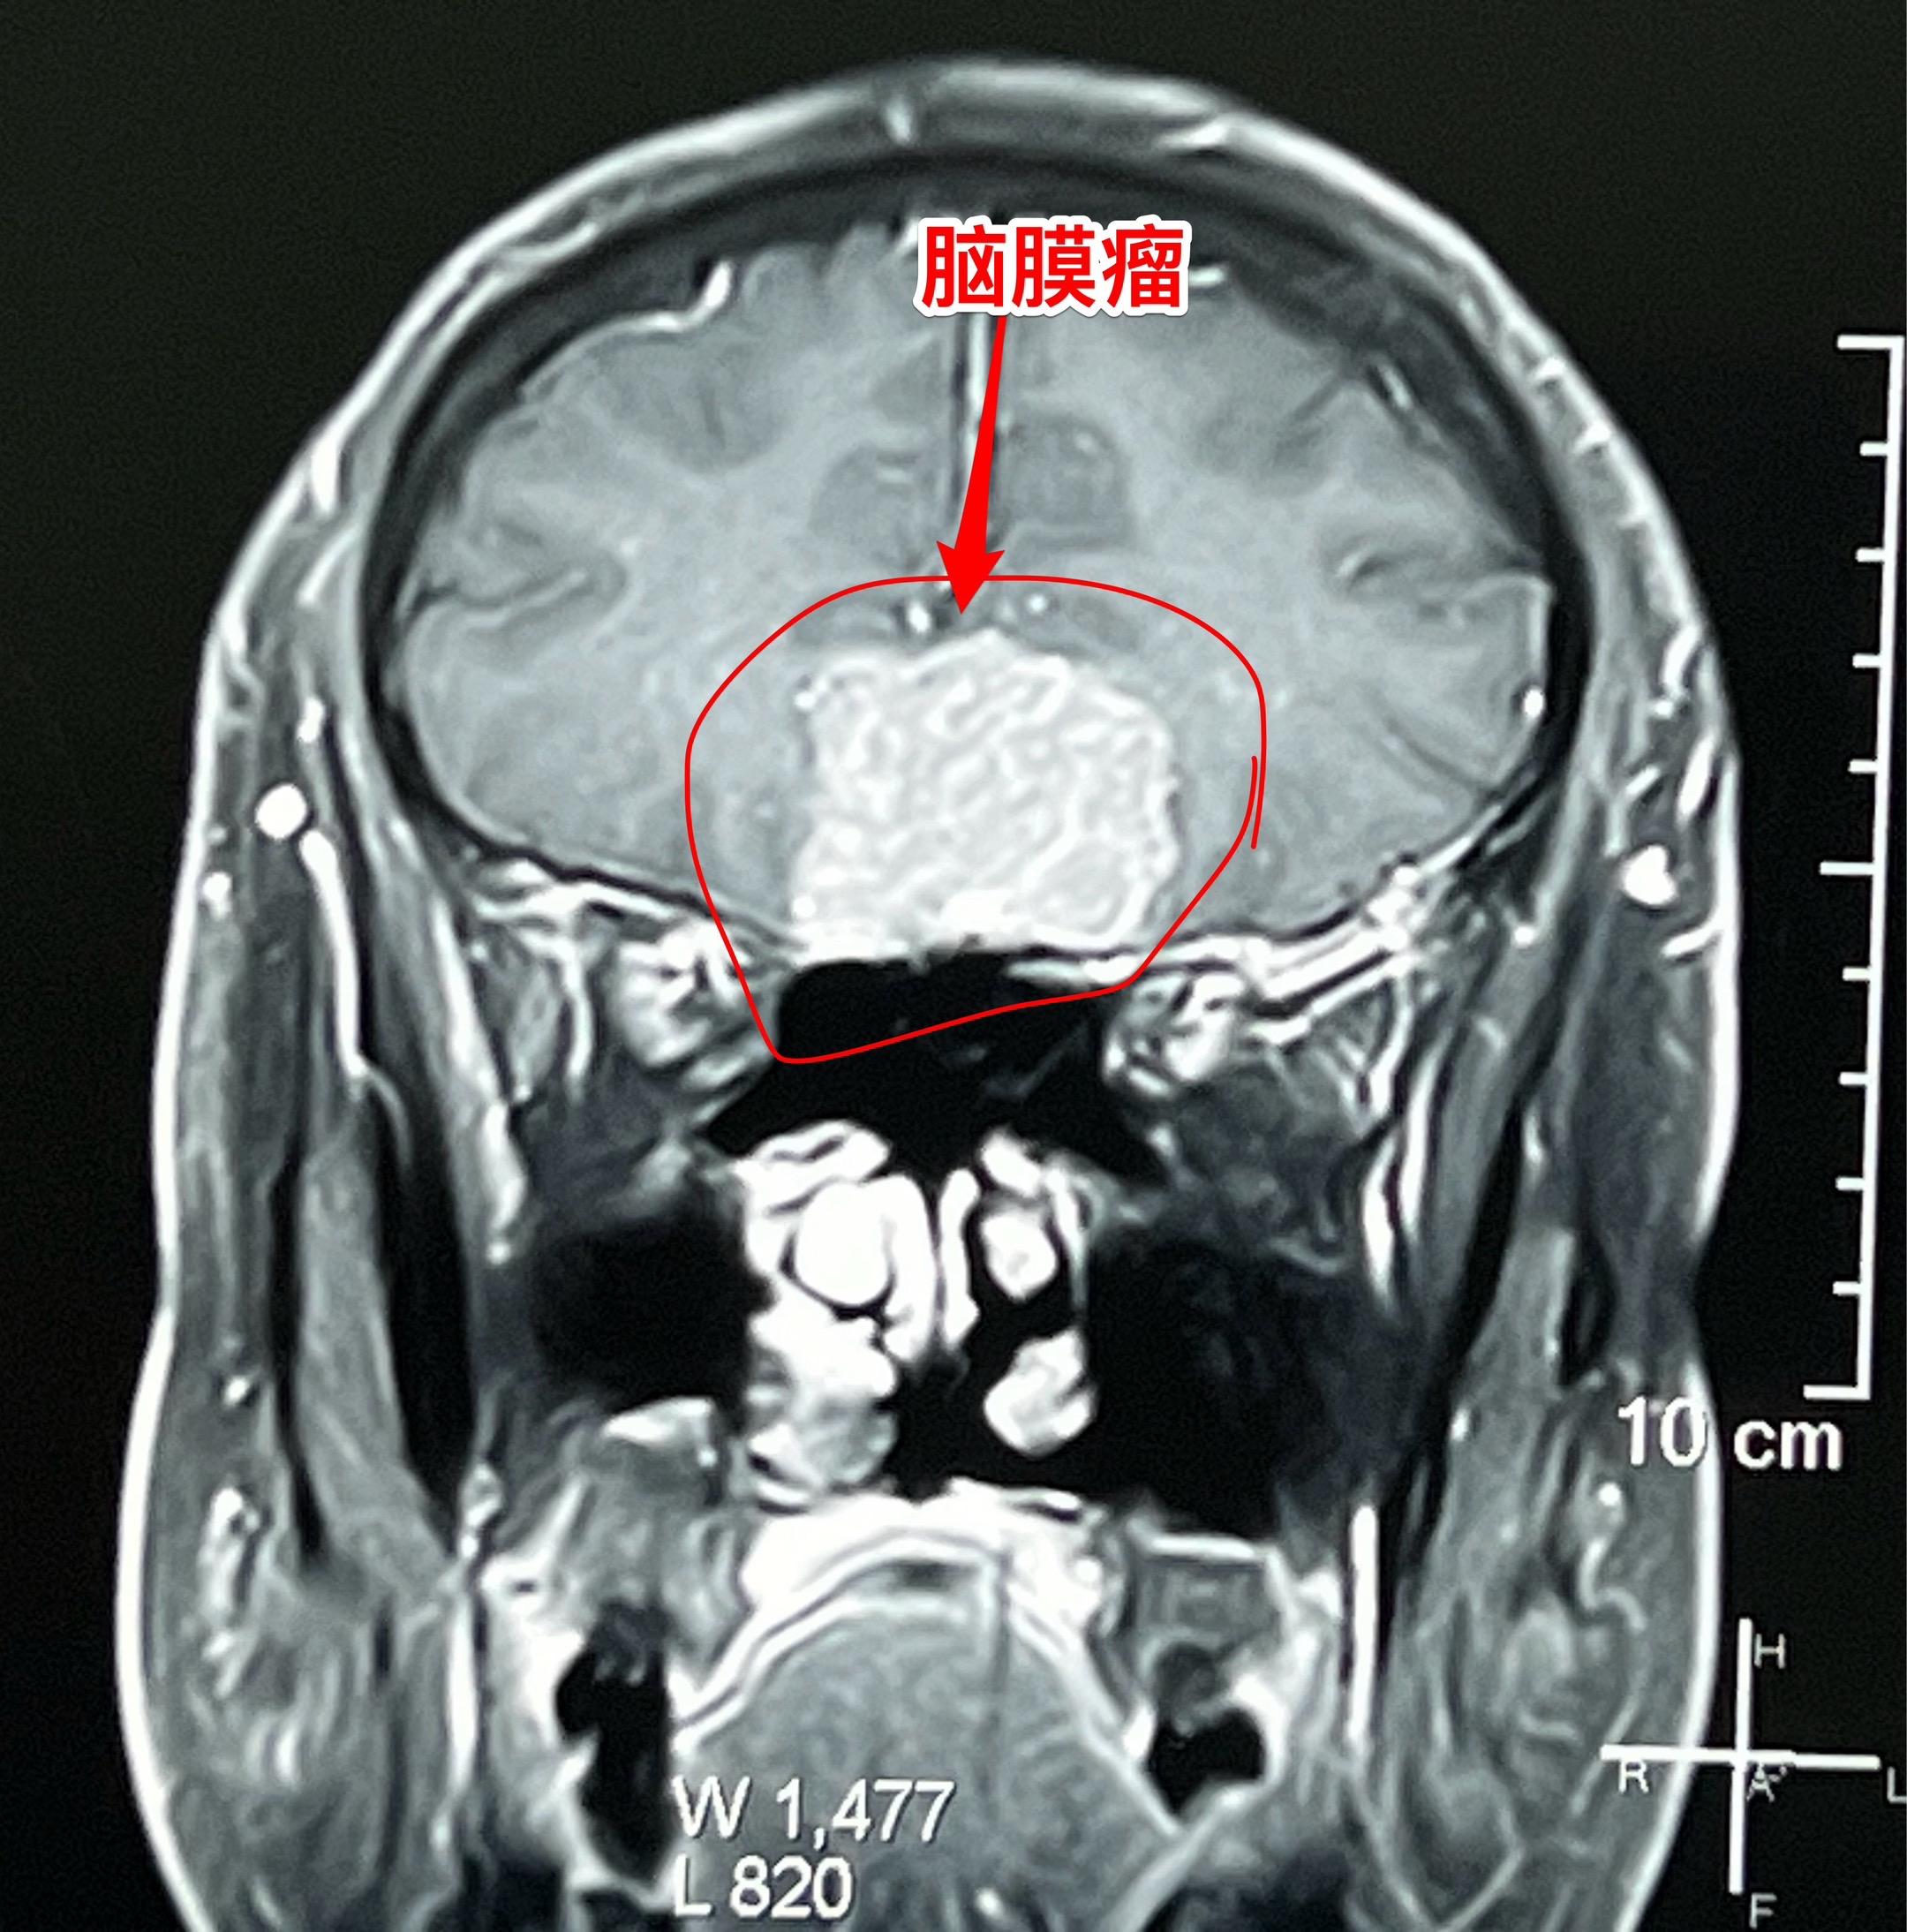

颅底脑膜瘤,彻底切除是首选治疗。59岁男性,体检发现这个肿瘤,无头痛症状,无视力下降,怀疑是脑膜瘤。 2025年10月30日作了手术,术中证实是脑膜瘤,肿瘤有完整包膜。彻底切除,争取治愈。